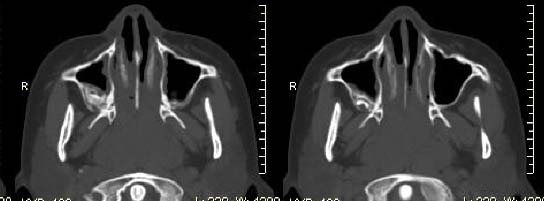

以下是引用随光逐影在2009-6-4 21:13:00的发言:[br]1)考虑鼻咽腺样体重度肥大。2)双侧鼻腔炎性改变。3)双侧上颌窦、双侧筛窦及左侧蝶窦炎症。

以下是引用zsl6918在2009-6-5 7:42:00的发言:[br]首先考虑鼻咽腺样体重度肥大,鉴别纤维血管瘤.强化有助明确.